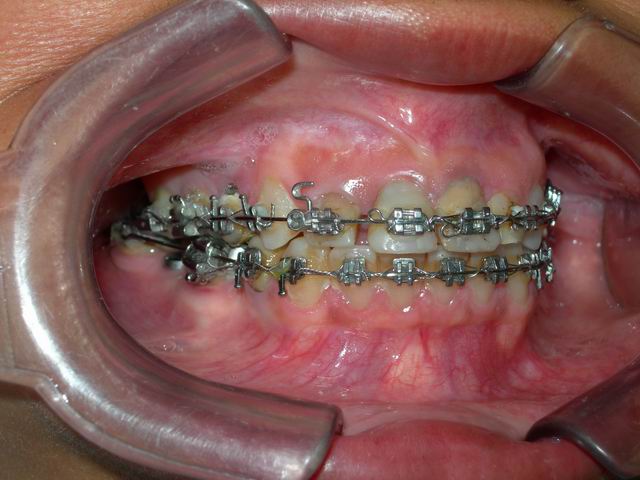

Tratamento ortodôntico prévio (vista frontal)